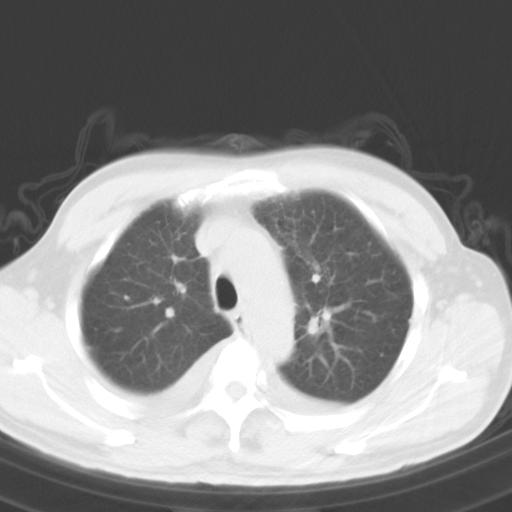

以下是引用zjzjr在2010-3-21 17:39:00的发言:[br]右下中心型肺癌并阻塞性肺炎/不张,纵膈淋巴结肿大,右侧大量胸腔积液,左侧少量胸腔积液

以下是引用zxl51642在2010-3-21 17:06:00的发言:[br]右下中心型肺癌并阻塞性肺炎/不张,纵膈淋巴结肿大,右侧大量胸腔积液,左侧少量胸腔积液,少量腹水。建议纤维支气管镜进一步检查。